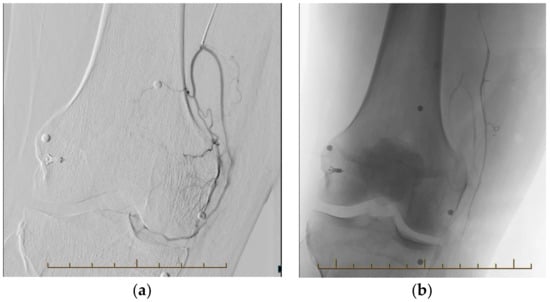

3.2. Procedural Technique

4.1. Post Arthroplasty Knee Pain